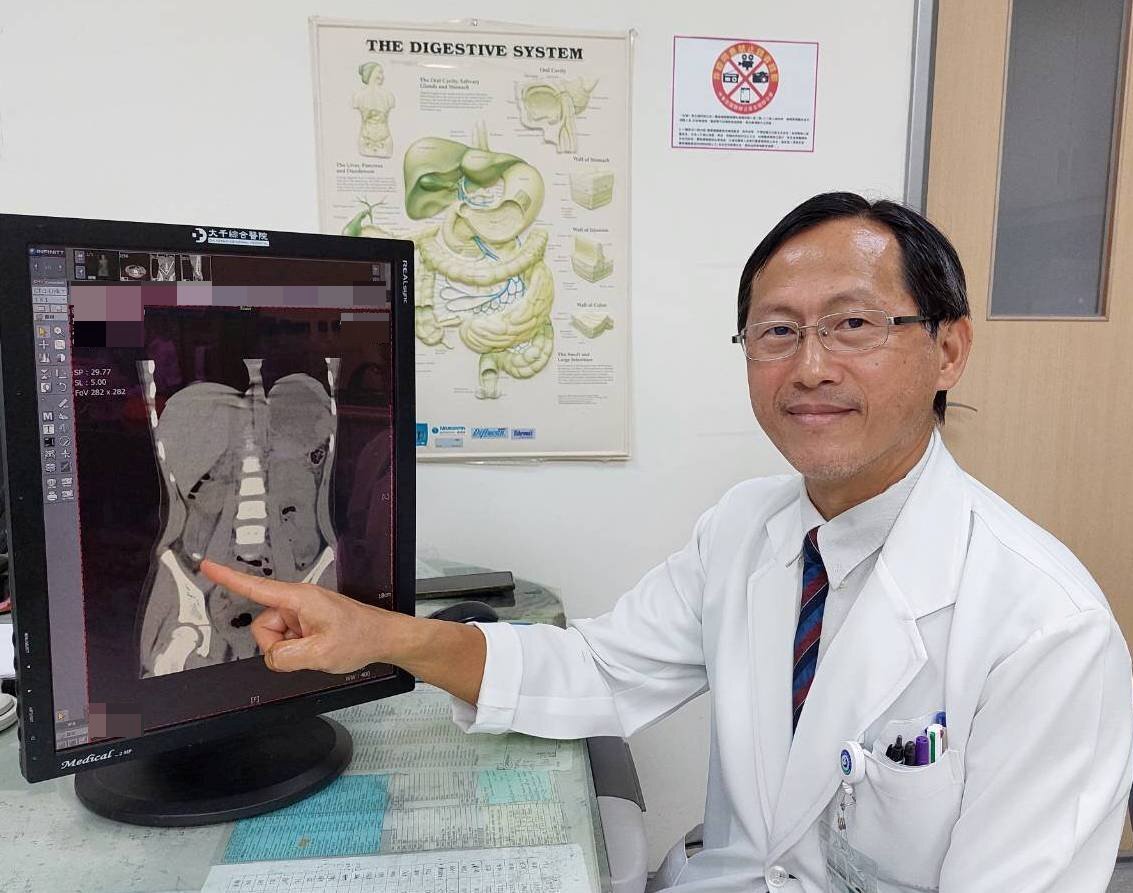

▲ 馮啟彥主任表示,急性闌尾炎發生在4歲幼童身上非常罕見。(圖/大千綜合醫院)

大千綜合醫院外科部主任馮啟彥指出,急性闌尾炎在兒童中多發生於12至18歲之間,10歲以下的病例已屬少見,而此次發生在4歲幼童身上更是罕見,容易被誤診。幸運的是,醫療團隊迅速採取腹腔鏡微創手術,成功切除闌尾並移除糞石,同時將腹膜炎膿瘍引流乾淨。術後,小女孩的身體恢復狀況良好,並於5天後順利出院。

馮啟彥主任進一步解釋,雖然腹腔鏡微創手術已廣泛應用於各類疾病的治療,但在年幼的孩童身上執行卻充滿挑戰。由於幼童體重輕、腹腔空間小,操作腹腔鏡的手術器械相對困難。此外,手術全程需控制腹壓不能過高,加上此次案例中闌尾破裂引發腹膜炎及腸沾黏,進一步提高了手術的難度。